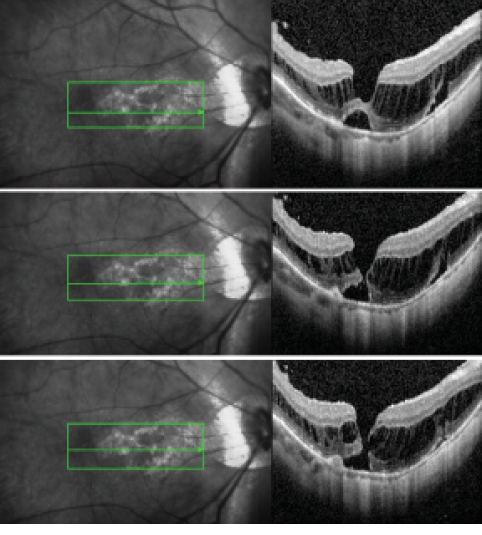

Figure 2. High-resolution and wide view swept-source OCT images demonstrate microstructural changes of the retina and adherent posterior vitreous cortex.

We also emphasize the importance of precise examinations using optical coherence tomography (OCT) during follow-up of MTM. To detect early FRD or micro-MH, thin-slice volume scans of OCT are useful to detect microstructural changes in the fovea (Figure 1). Swept-source OCT is also helpful to evaluate a wide area of the vitreoretinal surface for the presence of partial or complete posterior vitreous detachment (PVD), ERM, disruption of ILM, and determination of the thickness of the nerve fiver layer before vitrectomy (Figure 2).